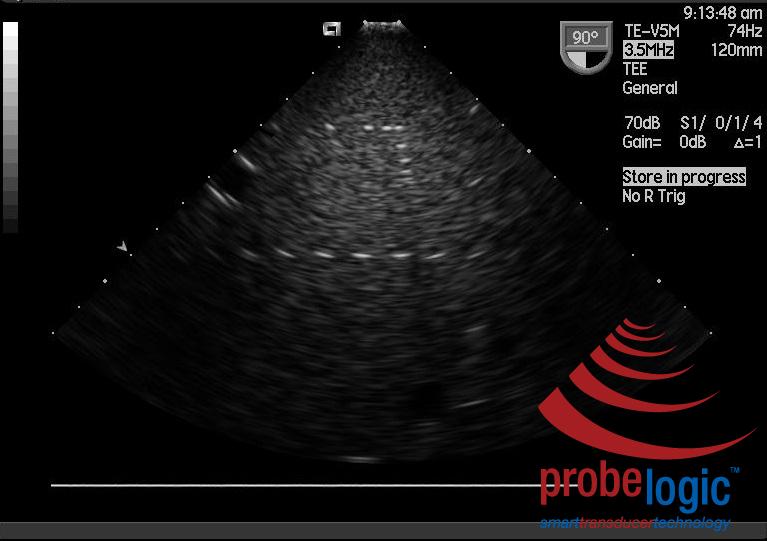

Now comparing with an image taken from the faulty probe:

With such gradual deterioration, it is sometimes difficult to recognize the problem as it just gets more and more difficult to scan patients. Get your probes acoustically tested today to be sure.